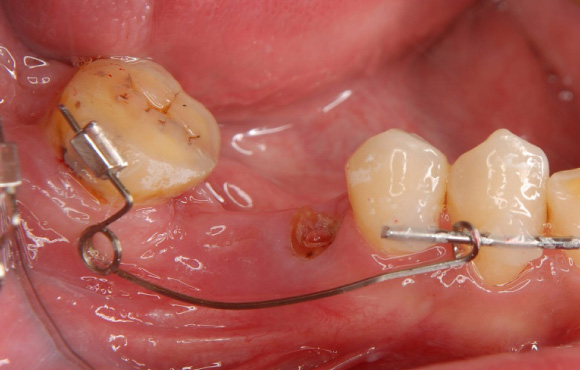

症例

手前の歯を喪失したあと、長い間放置したため手前に歯牙が傾いてしまっています。

歯牙を4か月から6か月かけて起こすことができました。

③引っ張り上げたことで歯茎の位置も変化するため適切な位置に歯茎を移動させるための歯周外科処置を行います。

④被せ物ができるだけの十分な歯質を得ることができました。

⑤その後、ハイブリッドクラウンで被せ物をセットしました。